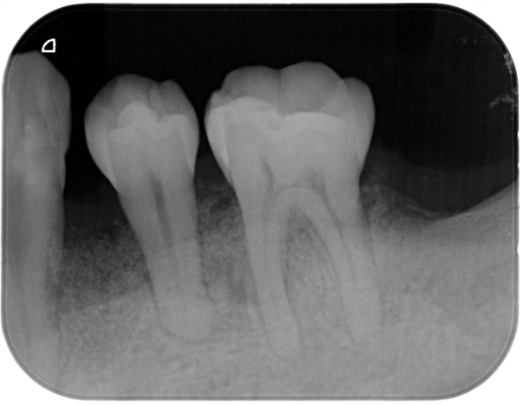

症例2

| 患者様データ | 50代 女性 |

| 来院時の主訴 | 「歯茎から出血する。口の中が全体的に痛い。」 |

| 医院の診断 | 重度の歯周病(壊死性潰瘍性歯周炎) |

| 通院期間 |

2年 |

| 来院回数 | 24回 |

| 治療費 | 総額:220,000円(税抜)+歯周基本治療は保険適用診療 【内訳】 保険適用診療:歯周病検査・歯磨きや生活習慣指導・歯石取りクリーニング 自由診療:歯周組織再生療法220,000円(費用は範囲によって異なります。) |

| リスクと副作用 | 定期的なメインテナンスが必要、正しい歯磨き習慣・生活習慣が必要不可欠 |

| ここがこだわりのポイント!☝ | 少しチャレンジングは症例ではありますが、歯周病によって無くなってしまった歯周組織(歯根膜・セメント質・骨・歯肉)が手術により改善しました。 |